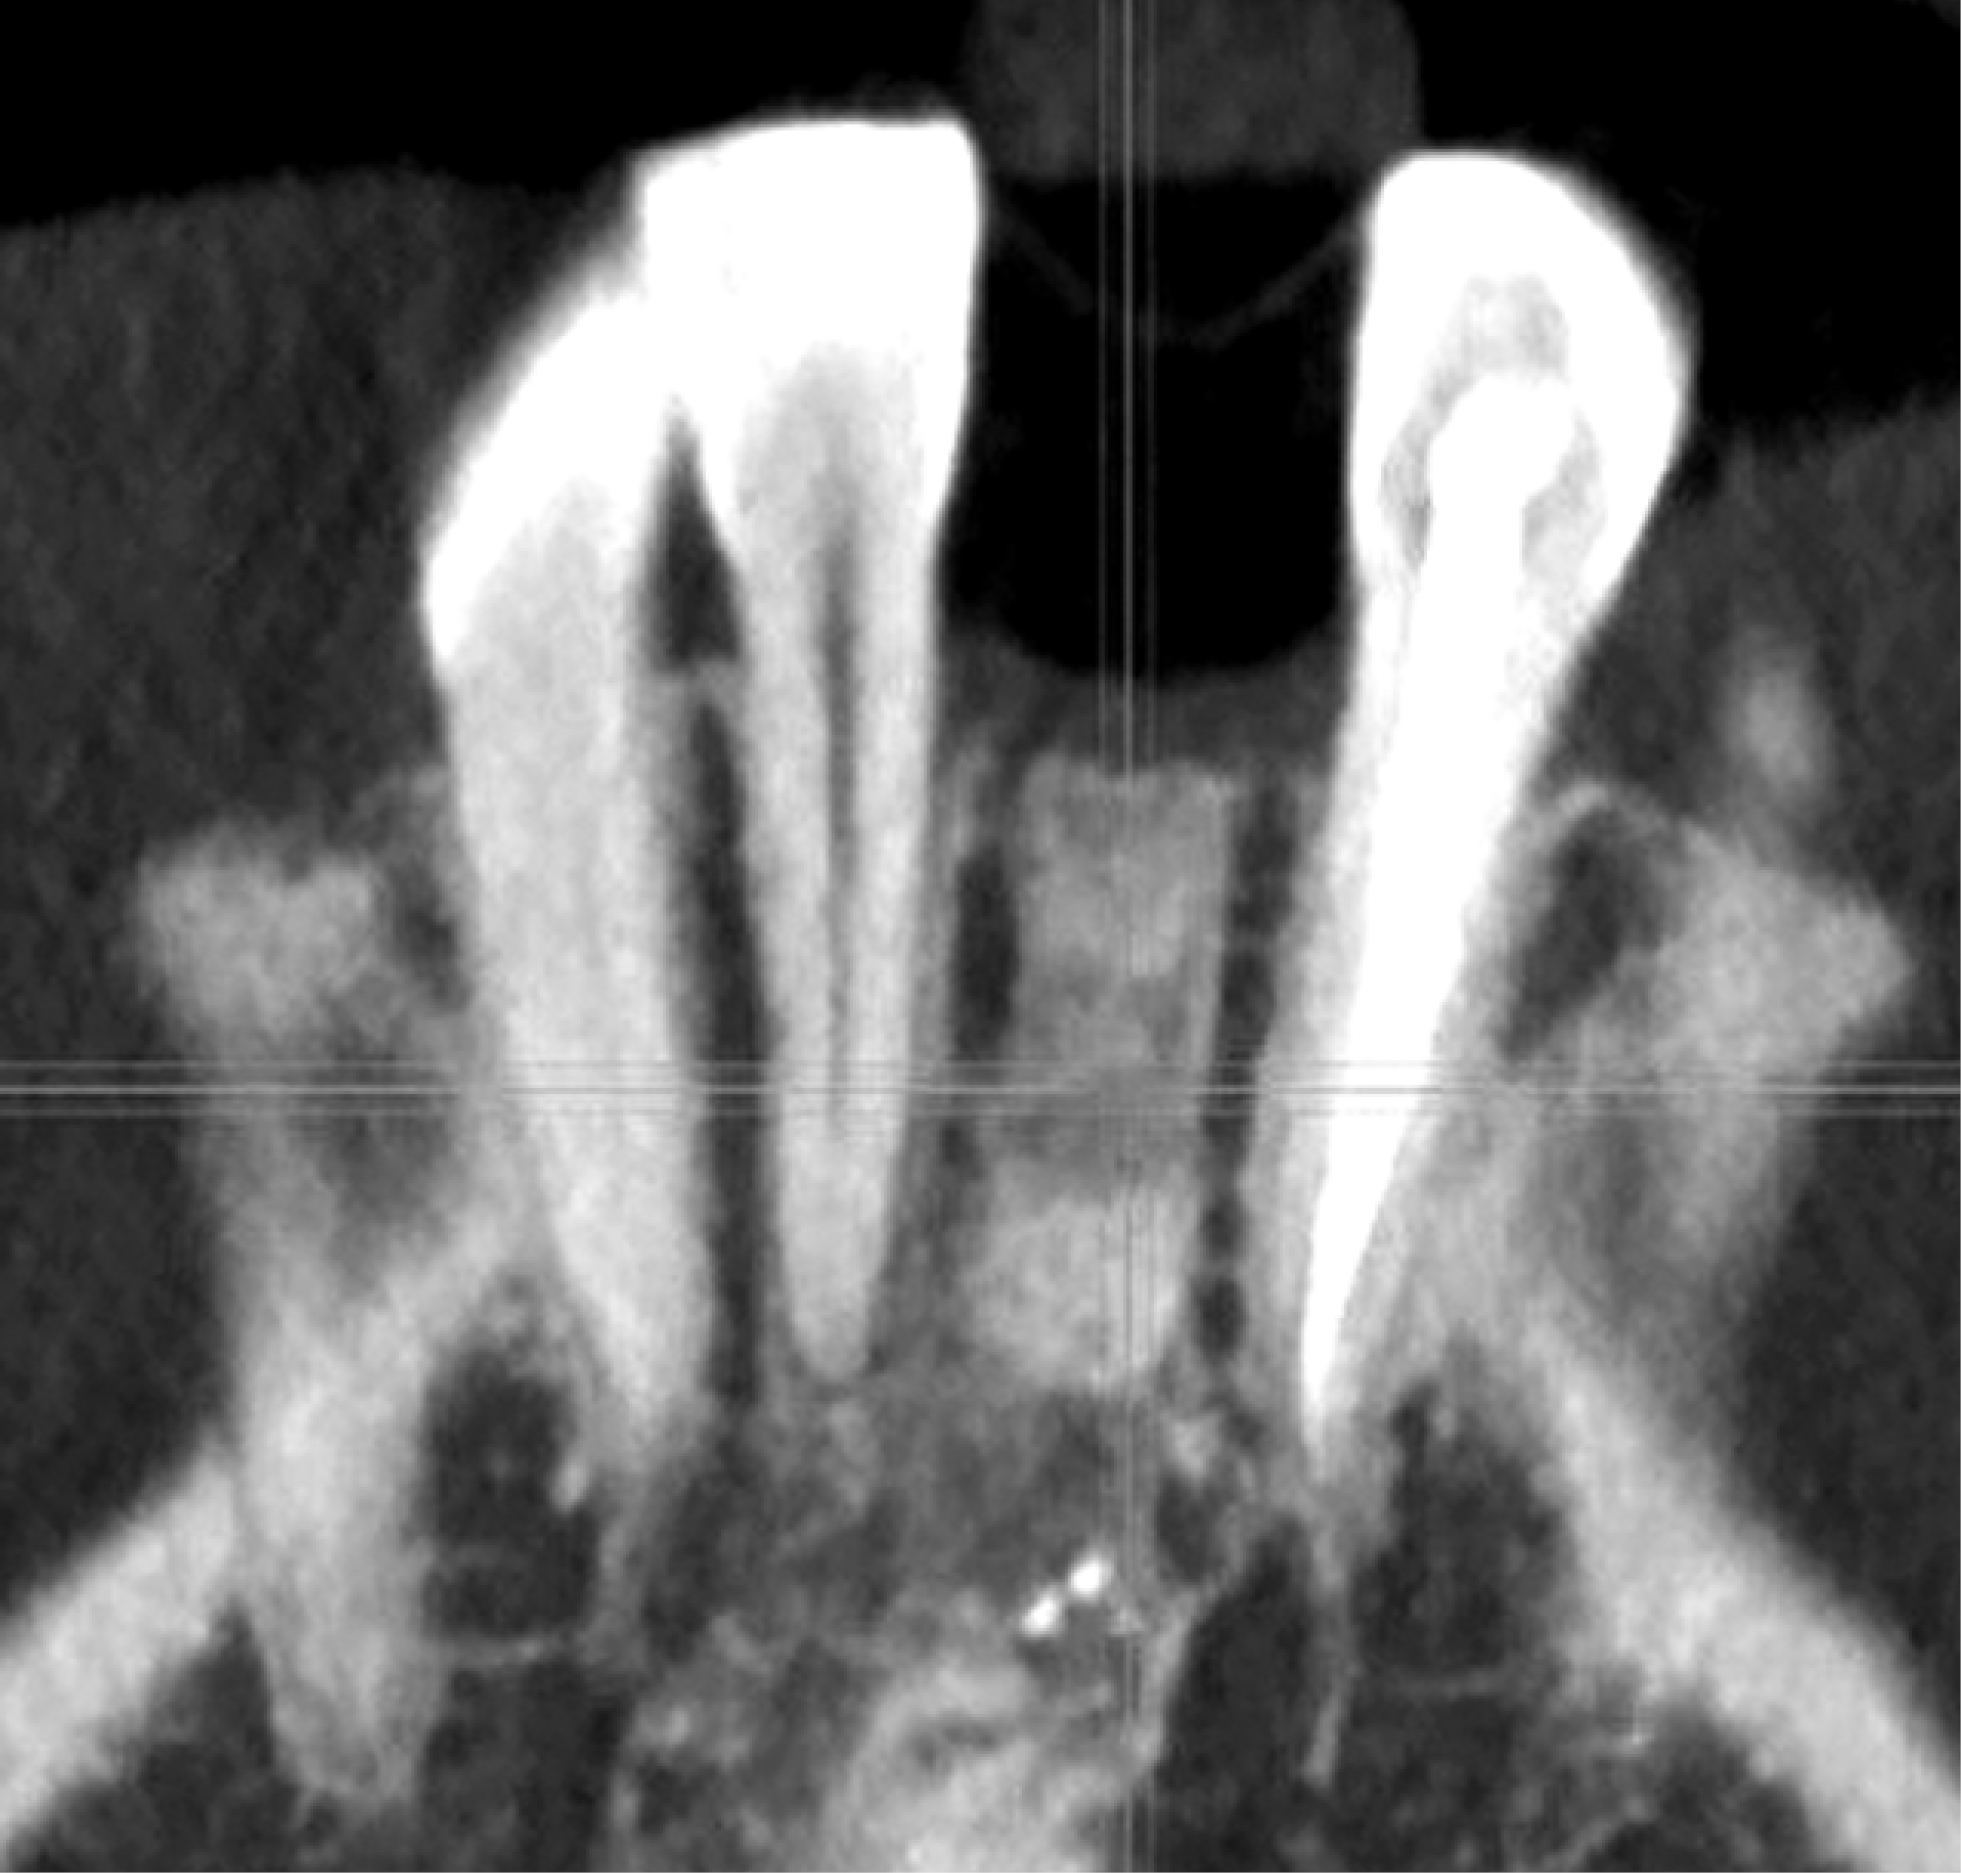

Пациентам 2-й группы (рис. 3) применяли комбинацию материалов Bio-Oss, Bio-Gide (Geistlich Pharma AG, Швейцария). Отмечается хороший показатель плотности кости. При гистологическом описании наблюдается наличие небольшого количества остеобластов, визуализируются остеоидные структуры, молодые костные трабекулы, базофильные участки с хаотично расположенными коллагеновыми волокнами (рис. 4).

Рис. 3. Сагиттальная плоскость области костной пластики материалами Bio-Oss, Bio-Gide спустя 5 мес. Конусно-лучевая компьютерная томография